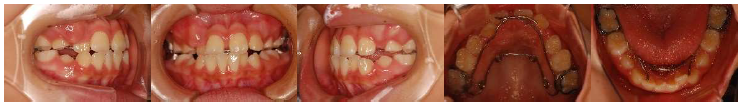

初めて当院へいらしたときのお口の中の写真(口腔内写真)です。検査の結果、大人の歯が生えるスペース確保のために顎を広げることと、前歯のかみ合わせを治すために部分的にワイヤーを使って歯並びを治すことになりました。